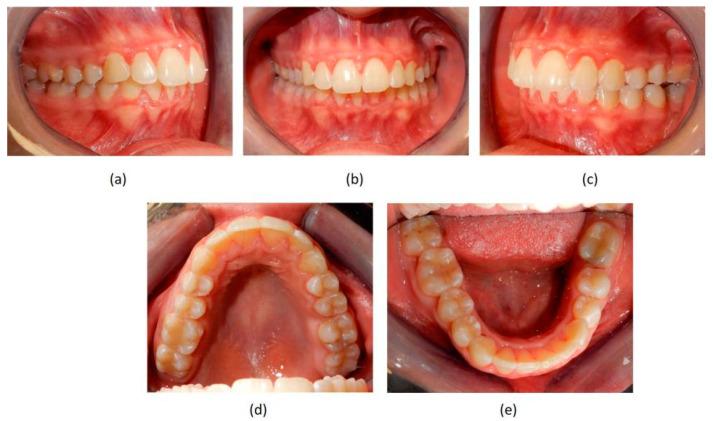

Successful closure of edentulous spaces with clear aligners (CAs) is influenced by many factors. CAs are tailored orthodontic devices whose predictability may have relevant medico-legal implications. This study presents a scoping review about missing molar space closure (MMSC) with CAs and a clinical case. This study aims to highlight the feasibility of molar space closure by mesialization with CAs without hybrid supports. Following PRISMA Sc-review guidelines, English-written randomized/non-randomized/observational clinical studies on PubMed, Scopus, Cochrane and Lilacs were searched. An 18-year-old patient, with upper and lower edentulous spaces due to the loss of two first molars, was rehabilitated with CAs (Sorridi, Sorridi srl, Latina, Italy) without hybrid supports and attachments. The therapy was carried out over 10 months. Currently, there are no studies documenting MMSC by mesialization with only CAs. Existing articles document the closure of premolar or incisor spaces. The upper and lower left second molars replaced the missing first molars, and erupting third molars replaced adjacent teeth. The biomechanical effects in space closure with CAs related to extraction cases appear as priorities of clinical/medico-legal interest. Our case turns attention to this movement of CAs without attachments/hybrid supports, indicating that even such a complex treatment can be comfortable for patients and safely predictable for specialists.

使用透明矫治器(CA)成功关闭无牙间隙受多种因素影响。CA是定制的正畸装置,其可预测性可能具有相关的医疗法律意义。本研究呈现了一项关于使用CA关闭缺失磨牙间隙(MMSC)的范围综述及一个临床病例。本研究旨在强调在无混合支持的情况下通过CA近中移动关闭磨牙间隙的可行性。遵循PRISMA范围综述指南,检索了PubMed、Scopus、Cochrane和Lilacs上英文撰写的随机/非随机/观察性临床研究。一名18岁患者因两颗第一磨牙缺失导致上下无牙间隙,使用CA(Sorridi,Sorridi srl,拉蒂纳,意大利)进行修复,无混合支持和附件。治疗持续了10个月。目前,尚无研究记录仅通过CA近中移动关闭MMSC的情况。现有文章记录了前磨牙或切牙间隙的关闭。上下颌左侧第二磨牙替代了缺失的第一磨牙,萌出的第三磨牙替代了相邻牙齿。与拔牙病例相关的CA关闭间隙的生物力学效应似乎是临床/医疗法律关注的重点。我们的病例将注意力转向了无附件/混合支持的CA这种移动方式,表明即使是如此复杂的治疗对患者来说也可以是舒适的,对专家来说也可以是安全可预测的。